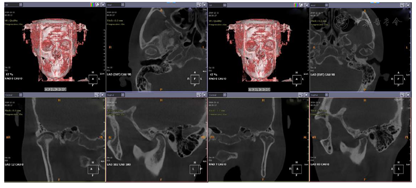

面充填物,未见根充物,根尖无明显异常(图4)。CBCT示:双侧髁突形态不对称,左侧髁突表面中央凹陷,余骨质未见异常(图5)。